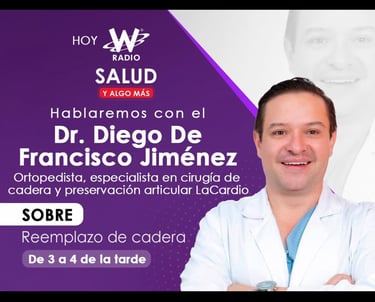

MD. Diego De Francisco Jiménez

Experto en cirugía de cadera y preservación

Soy médico cirujano especializado cirugía de cadera y preservación articular con enfoque en técnicas mínimamente invasivas. brindo atención personalizada para pacientes jóvenes, adultos y adultos mayores con patología de Cadera